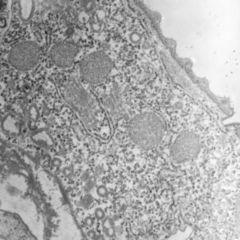

Histologic findings

Microscopically, the tumor cells recapitulate embryonic sensory retina or nonpigmented ciliary epithelium. The chalky grayish-white particles within the tumor mass correspond to foci of cartilage on histology; the semi-translucent membrane covering the lens in some tumors corresponds to spreading neoplastic cells.

Tumor cells form a characteristic diktyomatous pattern, with folded cords and sheets resembling a fisherman's net. In early development of the retina, the medullary epithelial cells acquire polarity, such that a basement membrane associated with the vitreous forms the internal limiting membrane on one side, while terminal bars form the outer limiting membrane on the other side. Proliferating tumor cells of diktyoma maintain the same polarity, arranged in cords and sheets folding back upon themselves. Depending on the direction of the folding, some folds surround fluid collection, while others do not. These fluid-filled spaces correspond to the grossly observed small cysts, which are mainly composed of vitreous humor.